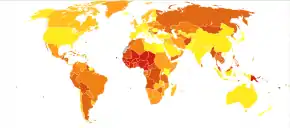

Epidemiology

Appendicitis is most common between the ages of 5 and 40.[98] In 2013, it resulted in 72,000 deaths globally, down from 88,000 in 1990.[99]

In the United States, there were nearly 293,000 hospitalizations involving appendicitis in 2010.[13] Appendicitis is one of the most frequent diagnoses for emergency department visits resulting in hospitalization among children ages 5–17 years in the United States.[100]

The standard treatment for acute appendicitis involves the surgical removal of the inflamed appendix.[6][11] This procedure can be performed either through an open incision in the abdomen (laparotomy) or using minimally invasive techniques with small incisions and cameras (laparoscopy). Surgery is essential to reduce the risk of complications or potential death associated with the rupture of the appendix.[3] Antibiotics may be equally effective in certain cases of non-ruptured appendicitis.[15][7][16] It is one of the most common and significant causes of sudden abdominal pain. In 2015, approximately 11.6 million cases of appendicitis were reported, resulting in around 50,100 deaths worldwide.[8][9] In the United States, appendicitis is one of the most common causes of sudden abdominal pain requiring surgery.[2] Annually, more than 300,000 individuals in the United States undergo surgical removal of their appendix.[17] Reginald Fitz is credited with being the first person to describe the condition in 1886.[18]